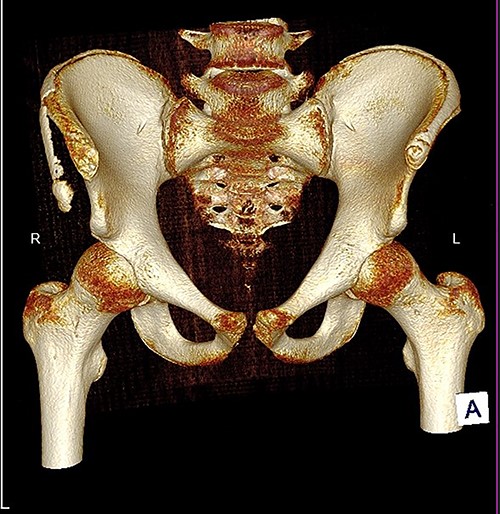

The anterior–posterior plain film X-Ray of pelvis demonstrated an avulsion fracture of the right ASIS and IC apophysis with 1.5 cm displacement (Fig. 1). Lateral view of the hip showed no extension into the joint. There was no radiological evidence of chronic overuse or previous injury. Computed tomography (CT) imaging was performed to better identify the injury; 3D volume reconstruction clearly demonstrated the unique fracture pattern of an ASIS avulsion in addition to an avulsion of the distal iliac apophysis extending ~5 cm with the described displacement (Figs 2–4).

3D reconstruction of tomographic CT scan illustrating avulsion fracture of ASIS and IC apophysis with its latero-inferior displacement (P - Posterior).